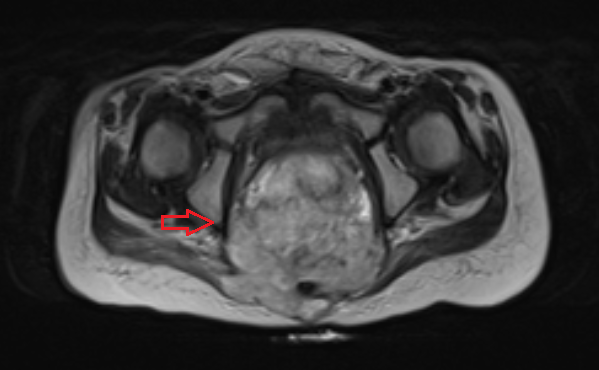

Яичники

Овариальные (расположенные в яичниках, яичниковые) опухоли наиболее часто проявляются болью в животе. При осмотре пальпируется опухоль в малом тазу, часто - в брюшной полости. Также за счет асцита (скопления в брюшной полости жидкости) увеличен живот. Нередко у девочек с таким диагнозом бывает лихорадка.

Самая часто диагностируемая герминогенная опухоль - это дисгерминома. Преимущественно ее обнаруживают во второй декаде жизни. У маленьких девочек встречается редко. Такое заболевания сравнительно быстро распространяется, поражая брюшину и второй яичник. Обычно новообразования односторонние, имеют большие размеры. В связи с этим частое явление - разрыв капсулы новообразования.

Рисунок 3. - тератома яичника а -УЗИ, б — МРТ.

- УЗИ. «Ультразвук» нужен для того, чтобы выявить первичный очаг как гонадной (в половых органах), так и внегонадной герминогенной опухоли. Его также проводят в ходе терапии, чтобы оценить ее эффективность.

- КТ (расшифровка: компьютерная томография), МРТ (расшифровка: магнитно-резонансная томография), ПЭТ-КТ (расшифровка: позитронно-эмиссионная томография, совмещенная с КТ). Эти обследования необходимы, чтобы рассмотреть структуры организма послойно и визуализировать опухоль. Они показывают, как сильно распространен патологический опухолевый процесс на находящиеся рядом ткани и органы, есть ли поражение костей. КТ - это самый чувствительный метод для обнаружения метастазов в легких. Проведение МРТ и КТ головного мозга необходимо, чтобы обнаружить и визуализировать герминогенные новообразования эпифиза.

Особенности течения заболевания определяются локализацией, размером и степенью злокачественности неоплазии. Типичными симптомами герминогенных опухолей яичника являются боли в животе различной интенсивности в сочетании с нарушениями менструального цикла. У детей последний признак отсутствует, что обуславливает отсутствие настороженности в отношении поражения внутренних половых органов на начальных стадиях заболевания. При прогрессировании герминогенных опухолей к перечисленным симптомам присоединяются увеличение живота и нарушения мочеиспускания. При пальпации на начальных стадиях определяется округлый, умеренно подвижный узел с четкими контурами. В последующем узел увеличивается в размере, возникают увеличение и деформация живота. На поздних стадиях выявляется асцит и нарушения функций различных органов, обусловленные отдаленным метастазированием.